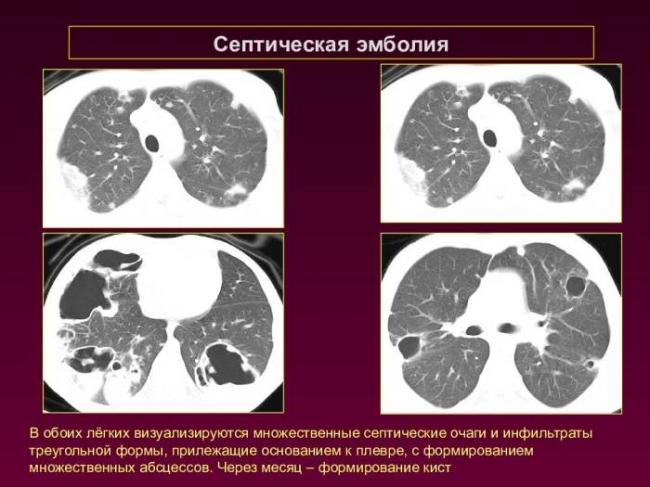

- Хаотично расположенные очаги. Такие образования характерны для патологических гематогенных процессов. Это может быть гематогенная инфекция, туберкулёз или метастазы гематогенного типа. Большие множественные очаги, размером около 10 мм, частенько наблюдаются при септических эмболиях, гранулематозе, грибковых инфекциях и метастазах. Все эти заболевания имеют некоторые отличия, по которым их можно дифференцировать.